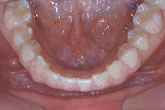

Ⅳ. 교정 치료 결과 및 차후 치료 계획

교정치료 후 debonding과 함께 상악 6전치 설측면에 .0195 twistflex를 사용한 lingual bonded retainer를 부착하였다. space closure와 함께 gingival bunching이 중절치 부위에 나타나 있음으로 충분히 기다린 후 (6개월 정도) 최종 보철물을 시행하기로 계획하였다.

최종 보철물 시행 시 필요하면 양 중절치  부위에 치은성형술 개념의 gingivectomy를 시행하고 다음과 같은 보철 치료를 계획하였다 (그림 7,8).

1) 측절치 임시보철물의 근심면을 삭제 (1mm 정도)

2) 중철치의 laminate 수복 (폭경은 1mm, 장경은 2mm 정도 증가)

3) 중철치 형태에 맞추어 측절치 최종보철 수복

그림 7. 증례환자의 교정치료 후 모습으로 차후 중절치 부위의 치은성형술과 함께, 측절치 임시보철물의 근심면 삭제 후 중절치의 라미네이트 수복(폭경은 1mm, 장경은 2mm 증가) 그리고 측절치의 최종보철로 심미적 보철물을 기대할 수 있다.